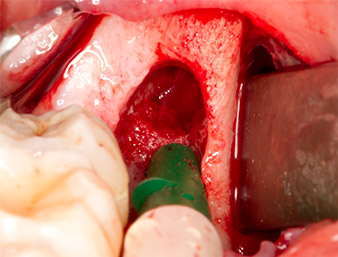

After block and local anaesthesia, the operating site was opened up and the soft tissue exposed for buccal retromolar access (Fig. 3).

The tissue above the root remnant was not completely ossified and consisted for the most part of granulation tissue modified by inflammation (Fig.4).

To obtain autogenous material for subsequent wound treatment, healthy bone chips were harvested from the surroundings of the root remnant with a piezo surgical instrument (Piezomed B5) (Fig. 5).